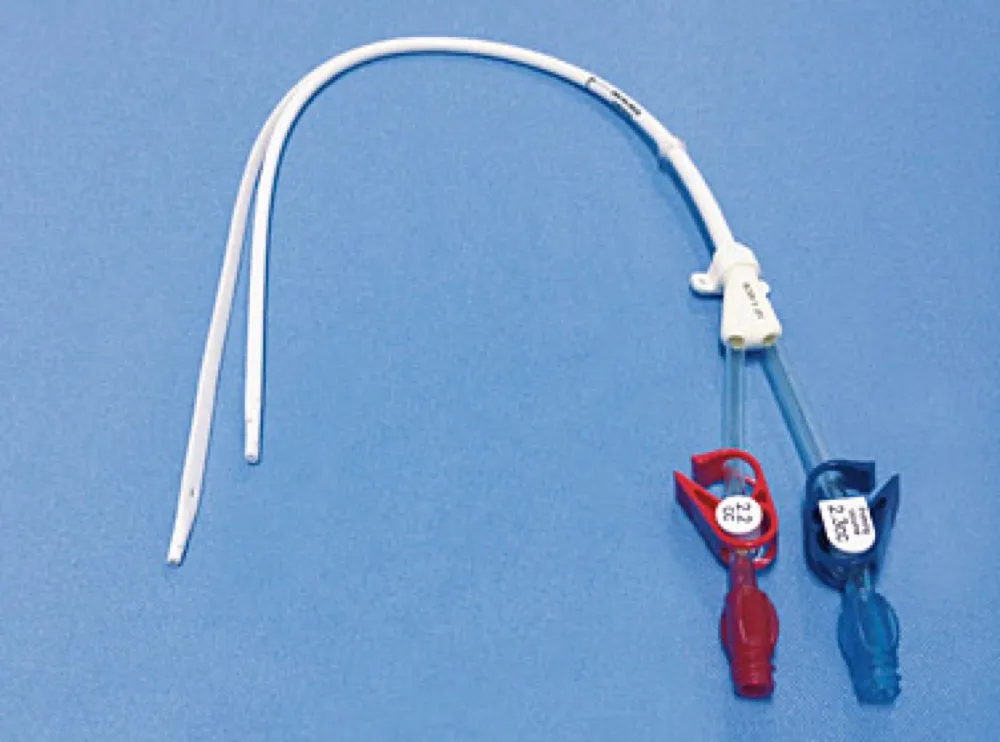

A DRPAD não é contraindicação à DP — e, na prática, muitos pacientes têm resultados comparáveis à hemodiálise. O “porém” está na mecânica: rins/hepatomegalia podem reduzir tolerância a volumes, aumentar risco de hérnias e extravasamentos, e piorar desconforto respiratório. Com técnica adequada (cateter presternal ou lateral, volumes menores, cicladora noturna e decúbito supino), a maioria das barreiras é contornável. Neste post, revisamos quando a DP é ótima, quando exigir cautela e como ajustar a prescrição para segurança e qualidade de vida.